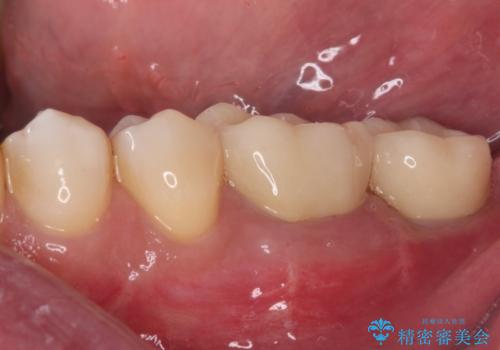

抜歯が必要な奥歯 ストローマン・インプラント補綴治療

- 近医にて奥歯の抜歯が必要と言われたとのことで来院された患者様です。

診査の結果、歯が破折しており、抜歯が必要な状態でした。

最後方歯であるため、入れ歯かインプラントかどちらかの補綴治療を行うこととなりますが、ご希望によりインプラント補綴治療を行うこととしました。

インプラントにはストローマン社のSLActiveを使用し、埋入から補綴までおよそ3か月と、短期間で治療を進めることができました。